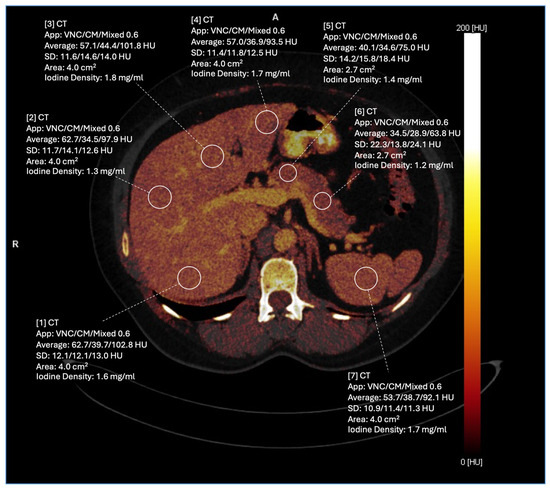

2.4. Iodine Mapping and Uptake Measurements